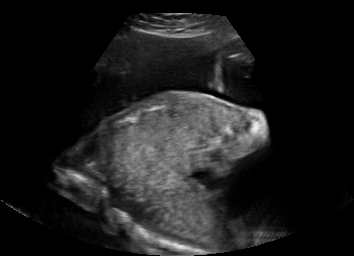

Real in-vivo images. 22 ultrasound sequences were collected using a GE Voluson E8 machine during standard fetal screening exams of 8 patients. Each sequence is several seconds long. We extracted all 4427 frames and resize them to , see Fig. 2 for some examples. The resulting image set was randomly split into training-validation-test sets by a 80-10-10% ratio.